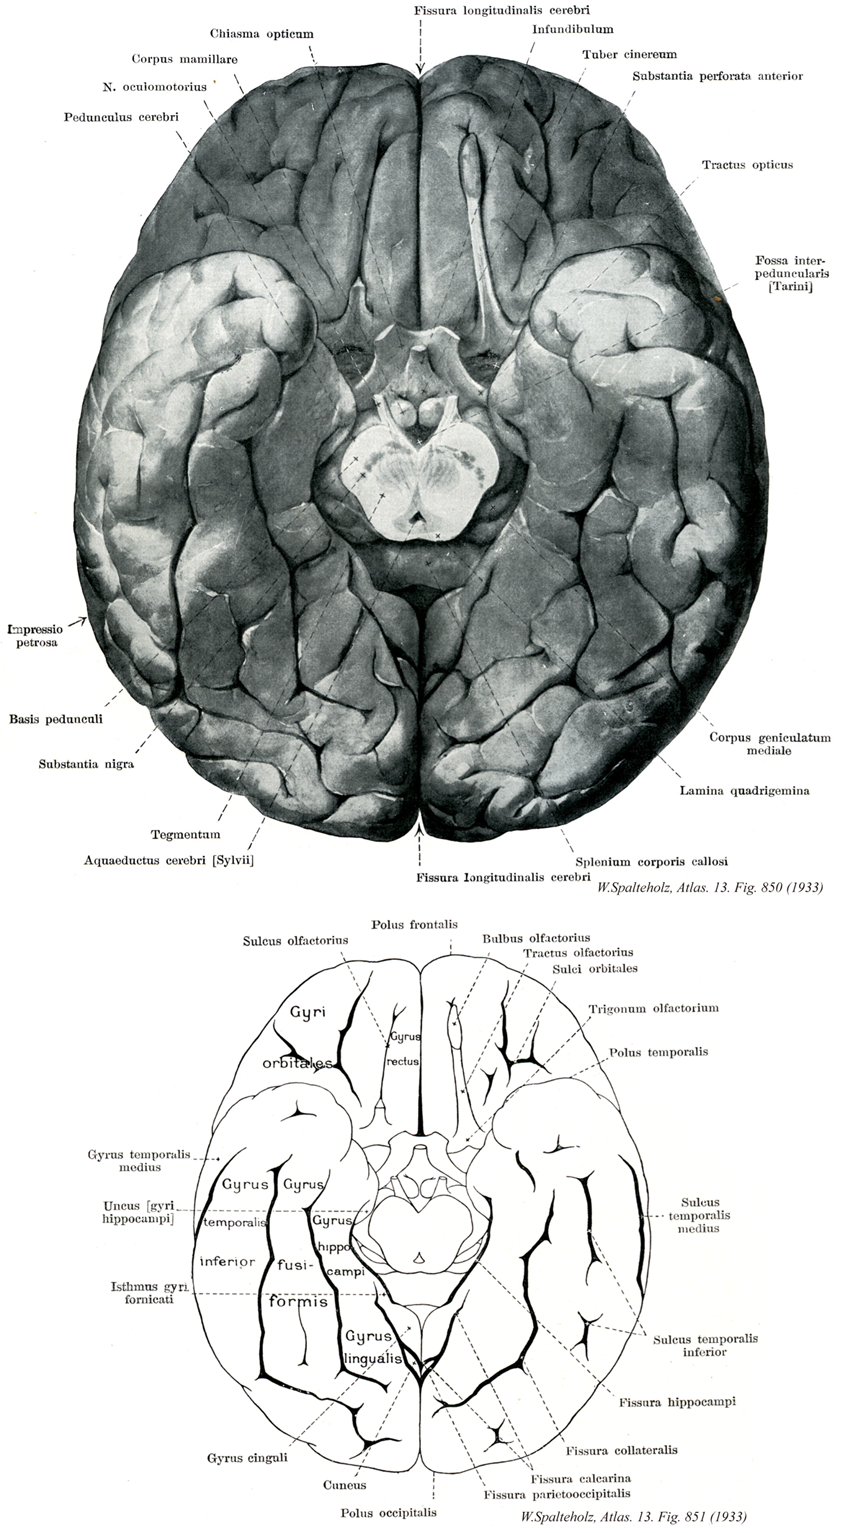

850

- 850_00【Cerebral hemisphere大脳半球 Hemispherium cerebri】

→(大脳半球は表層の外套と深部の大脳核からなる。外套は表面の灰白質である大脳皮質と、より深部の白質である大脳髄質からなる。しかし、TAによると英語では外套という用語がなく外套と大脳皮質を同義語としている。左右の大脳半球は大脳縦裂により分けられているが、その大部分は脳梁により結合されている。さらに大脳半球は大脳横裂により小脳と分けられている。外套の表面には多数の溝と、溝の間の隆起がみられ、それぞれ大脳溝および頭頂骨横行は葉間溝とよばれ、四つの大脳葉(前頭葉、頭頂葉、側頭葉、後頭葉)を区別する上で重要な溝である。外側口の深部には島とよばれる外套の一部がある。前頭葉の下面には嗅脳がある。大脳皮質は部位により構造上の差違があり、系統発生学的に古い古皮質および原皮質と新しい新皮質に大別される。新皮質は発生の途上で少なくとも一度は原則として6層形成を示すのに対して、古皮質および原皮質の発生のいかなる時期にも6層形成を示さず、嗅脳、海馬および歯状回などに限局してみられる。)

- 850_01【Optic chiasm; Optic chiasma視神経交叉;視交叉;視束交叉 Chiasma opticum; Chiasma fasciculorum opiticorum】 Decussation of medial optic nerve fibers between the optic tract and optic nerve.

→(視神経交叉は視床下部の漏斗の吻側にある扁平な線維板で、視神経線維が交叉しているところ。視交叉の背側から両側に開いて出る線維束は視索である。第三脳室の終板と灰白隆起の間で視交叉は第三脳室の底の一部を成す(視交叉陥凹)。視交叉はその上面で(終板の前方)前交連動脈と接し、下面はトルコ鞍の鞍隔膜の上に乗っている。眼球網膜の鼻側半からの線維は交叉して対側へ行き、側頭半からの線維は同側を交叉せずに後方へすすむ。下垂体前葉から発生する腫瘍が視交叉を圧迫することがある。)

- 850_02【Mammillary body乳頭体 Corpus mammillare】 Paired, rounded elevations on the floor of the diencephalon that are connected with the thalamus and mesencephalon.

→(乳頭体は有髄線維を豊富に含み、視床下部の乳頭隆起で内側および外側乳頭体核より成る。脚間窩に突出している左右1対の半球状の隆起、脳弓から海馬足の主要線維束を受け、視床前核と脳幹被蓋部とに線維を出す。内側乳頭体核は外側乳頭体核より大きいが、そのニューロンは比較的小さく、有髄線維のカプセルに包まれている。外側乳頭体核はずっと小さくて、「とくにヒトでは、見分けるのがむずかしい。」そのニューロンは内側乳頭体核のものよりも大きく、染色されやすい。乳頭体への入力線維は、海馬支脚(交連後部脳弓を介して)、視床下部腹内側核、中脳(乳頭体脚を介して)、などからくる。脳弓の線維数は非常に多い。脳弓線維は内側乳頭体核に終止するが、中には乳頭体を通り越して中脳被蓋ないし中心灰白質でシナプス結合するものもある。中脳から乳頭体への入力線維は、中脳中心灰白質および中脳網様体にある楔状核から起こり、乳頭体脚を通ってくる。乳頭体からの出力線維は大脳辺縁系の重要な要素である。内側乳頭体核から出る線維は明瞭な上行性線維束である主乳頭体束を作り、これは吻背側方へ向かう乳頭体視床路と、尾側方へ向かうこれよりも小さい乳頭体被蓋束に分かれる。乳頭体視床路線維は主として内側乳頭体核より起こり、視床前核群でシナプス結合する。視床前核は帯状回でシナプス結合する線維を出す。「海馬→脳弓→乳頭体→視床前核→帯状回」の回路は大脳辺縁系の中心的な回路としてしられている(Papezの情動回路)。乳頭体被蓋束の出力線維は内側乳頭体の背側部より起こり、中脳被蓋でシナプス結合する。)

- 850_03【Oculomotor nerve [III]動眼神経[脳神経III] Nervus oculomotorius [III]】 Nerve containing motor and parasympathetic fibers that exits the oculomotor sulcus and passes through the superior orbital fissure into the orbit.

→(動眼神経の主成分は動眼神経主核から出る体性運動性のもので外側直筋および上斜筋以外の眼筋を支配する。このほかに副交感性の動眼神経副核[Edinger-Westphal核]から出る線維が加わる。以上の2核から出る線維は多数の根をつくって大脳脚内側溝から出て1神経幹となり、滑車神経、外転神経および眼神経とともに、蝶形骨体の両側にある海綿静脈洞の上壁に沿ってすすみ、上眼窩裂を通って眼窩内に入り、上下の2枝に分かれる。上枝は上瞼挙筋および上直筋に、下枝は内側直筋、下直筋および下斜筋に分布する。また下枝からはきわめて短い動眼神経からの根が出て、毛様体神経節に入るが、これは動眼神経副核から出て、下枝を通って毛様体神経節に入る副交感線維にほかならない。)

- 850_04【Cerebral peduncle大脳脚[広義の] Pedunculus cerebri】

→(広義の大脳脚は中脳の腹側部で、背側の中脳蓋(四丘体)および中心灰白質背側部を除いた中脳水道水平中央断面より腹側の部分を総称する。さらにこれは背側の中脳被蓋と狭義の大脳脚に分かれる。中脳被蓋には著明な構造物として、動眼神経核群、中脳網様体、赤核、黒質、内側毛帯などが存在する。もともとは全脳と後脳を連結するやや細くなった首状部分である中脳の両半分の部分をさす名称であったが、その後、様々な意味で用いられるようになった。Crus cerebriとよばれる皮質投射線維の大きな束のみをさしたり、これに被蓋を加えたものをさしたりするが、後者の方が好ましい、脚底にある黒質は被蓋とcrus cerebriとを境する構造とみなされている。)

- 850_05【Petrous impression岩様圧痕;錐体圧痕 Impressio petrosa】

→()

- 850_06【Base of peduncle大脳脚底;脚底 Basis pedunculi; Basis pedunculi cerebralis】 Comparable to the cerebral crus.

→(狭義の大脳脚を指す。大脳脚の前部と同義語である。)

- 850_07Soemmering's substance【Substantia nigra黒質;黒核 Substantia nigra; Nucleus niger】 Black nucleus lying on the cerebral crura. It is characterized by pigmented ganglion cells making it visible to the naked eye. It extends through the entire mesencephalon into the diencephalon.

→(黒質は中脳被蓋腹側部の核で大脳脚の背側に接して存在する。ヒトの黒質の神経細胞は顆粒状のメラニン色素を豊富に含有するため、黒質は全体として肉眼的に黒くみえる。黒質には背側の緻密部と腹側の網様部が区分される。緻密部が神経細胞に富むのに対し、網様部では神経細胞の密度は粗で、細い神経線維に富む。したがて、前者は黒色部、後者は赤色部とよばれることがある。黒質からおこる遠心性神経線維としては、緻密部からおこり線条体に分布する黒質線条体線維、網様部から起こり視床のとくに内側腹側核(VM)に分布する黒質視床線維、および網様部からおこり上丘の中間灰白質に分布する黒質上丘線維などが主なものである。また、黒質に分布する求心性神経線維の起始としては、線条体・淡蒼球・視床下核(Luys体)が主なものである。これらのほか、前頭葉皮質・背側縫線核・扁桃体中心核・外側手綱核なども報告されているが不確実である。黒質は中枢神経系のうちでドーパミンとGABAの含有量が高い部位として知られる。ドーパミンは線条体に神経線維を送る黒質緻密部の神経細胞に主として含まれ、またGABAは線条体よりおこり黒質網様体に至る神経線維の軸索終末に主として含まれる。黒質に見られる線維はまたは11個のアミノ酸が連絡したペプチドとしてのP物質(SP)も含む。黒質は脳において最も高濃度にP物質を有する部位で、この物質は黒質の緻密部および緻密部内の神経終末に凝集している。網様部はまたエンケファリン作働性線維および終末も有する。尾状核および被殻の樹状突起の棘突起に含むニューロンから起こる線条体黒質線維はGABA、P物質、エンケファリンを含む。これらの線維は同様の伝達物質を有する線条体淡蒼球線維を出すニューロンとは異なる細胞集団から起こる。黒質はパーキンソン病(振戦麻痺)の原因となっている代謝障害に緻密に関係しており、Huntington舞踏病および異常な不随意運動や筋緊張の変化を特徴とする他のタイプの運動障害にも関与しているようである。パーキンソン病では黒質から線条体へのドーパミンの輸送および合成が極度に傷害される。Huntington舞踏病では線条体のドーパミンは正常であるがGABAは著明に減少している。)

- 850_08【Tegmentum of midbrain中脳被蓋 Tegmentum mesencephali】 Continuation of the gray substance of the fourth ventricle that forms the periaqueductal gray substance surrounding the cerebral aqueduct.

→(中脳被蓋は黒質から中脳水道にまでのびる中脳の大部分で動眼神経核、滑車神経核の他に網様体、赤核および多くの小さな細胞集団を含む。)

- 850_09Sylvius, Aqueduct of【Aqueduct of midbrain; Cerebral aqueduct中脳水道;脳水道 Aqueductus mesencephali; Aqueductus cerebri】 Narrow canal in the mesencephalon between the third and fourth ventricles.

→(中脳水道はシルビウス水道ともよばれる。中脳では脳室系は細い管となり、間脳の第三脳室と菱脳の第四脳室とを結合する。これを中脳水道と称し、横断面は円形または底辺を背側に向けた角のとれた三角形をなし、中心灰白質によってかこまれる。その存在については古くから知られていたが、フランスの解剖学者Jacobus Sylvius (1478-1555)の著書(1555年)で初めて説明がなされた。)

- 850_10【Longitudinal cerebral fissure; Longitudinal fissure of hemisphere大脳縦裂;半球間裂 Fissura longitudinalis cerebri; Fissura interhemisphaerica】 Deep longitudinal cleft that divides the cerebral hemispheres and houses the falx cerebri.

→(大脳縦裂は左右大脳半球の深い縦裂である。左右大脳半球は大脳縦裂によって不完全に分けられており、生体ではこの部分に大脳鎌が入り込んでいる。前頭部と後頭部では大脳半球は完全に分かれているが、中央部では大脳縦裂が幅広い半球間の交連線維群である脳梁までしか達していない。)

- 850_11【Infundibulum of pituitary gland漏斗(下垂体の) Infundibulum】 Pituitary stalk.

→(下垂体の漏斗は視床下部の腹側方の突出部とその中にある第三脳室の陥凹によって形成される。漏斗の最も遠位に突出した部分が下垂体後葉(神経下垂体)であり、漏斗の突出部と正中隆起を結合する組織は漏斗柄とよばれる。)

- 850_12【Tuber cinereum灰白隆起 Tuber cinereum】 Condensation of gray substance in the posterior wall of the infundibulum.

→(尾方は乳頭体、吻方は視神経交叉、両外側は視索で区切られ、腹部は漏斗および脳下垂体柄へとのびる視床下部底の隆起。これは灰白質の高まりで第三脳室底の一部を形成し、円錐状になって漏斗に終わる。)

- 850_13【Anterior perforated substance前有孔質;嗅野;嗅覚野 Substantia perforata anterior; Substantia perforata rostralis; Area olfactoria】 Perforated area between the olfactory striae produced by the passage of cerebral vessels. It transitions into the gray substance of the tuber cinereum and paraterminal gyrus.

→(前有孔質は嗅脳後部の大部分を占め、内側、外側嗅条と視索が嗅回をなしている。視床、大脳核、内包などにいたる小血管が出入りするため多数の孔が明いている。後縁はブローカの対角帯により形成される。)

- 850_14【Optic tract視索 Tractus opticus】 Portion of the visual pathway between the optic chiasm and lateral geniculate body that is visible on the surface of the basal part of the brain.

→(視索は視交叉と外側膝状体の間の視覚路で左右の視索は視床下部と大脳脚基底部を回って後外方へ走る。これらの線維の多くは外側膝状体の中に終止するが、小部分は下丘腕となって上丘および視蓋前域にまで続く。外側膝状体からは膝状体鳥距路が起こり、これが視覚路の最後の中継路をなす。視索前域は対光反射と関係し、上丘は眼と頭の反射運動より視覚刺激を追跡することと関係している。網膜視床下部線維は、両側性に視床下部の視神経交叉上核に終止する。この網膜からの直接の投射は、機能的には神経内分泌調節と関連している。)

- 850_15【Interpeduncular fossa脚間窩 Fossa interpeduncularis】 Depression between the cerebral crura.

→(脚間窩は左右の大脳脚間にある中脳後表面上の深い凹みで底面は出入りする小血管の為に多数の小孔を有する後有孔質によって形成される。)

- 850_16【Medial geniculate body内側膝状体 Corpus geniculatum mediale】 Part of the auditory pathway that is connected with the inferior colliculus.

→(内側膝状体は、視床の尾方腹側面で、外側膝状体の内側方、大脳脚の背方に位置する。この核は、視床における聴覚の中継核であって、聴放線を出す。下位脳幹にある聴覚の中継核群とは違って、両側の内側膝状体の間には交連線維による連絡がない。内側膝状体は、明瞭な細胞構築と連絡から更に幾つかの部分にに分けられる。内側膝状体は内側部、背側部および腹側部と呼ばれる三つの主要な部分から構成される。内側膝状体のこれらの細区分域は、普通の組織学的標本では区別するのが容易ではないが、Golgi標本では明らかである。内側膝状体腹側核は、内側膝状体の吻尾方向の全長にわたって広がり、内方が、下丘腕によって境されている。内側膝状体の他の大きな部分とは違って、腹側核には、明確な層板構造がある。腹側部の細胞の大きさと形は、かなり一定しており、房状の樹状突起をもつ。房状細胞の樹状突起と下丘腕の神経線維によってできた層状構造は、らせん形、または、弯曲した垂直の板状を示す。下丘からの求心性線維は特定の層板にはいり、そのまま同じ層と連絡しつづける。内側膝状体の側腹部にある層板構造は、外側膝状体のそれに類似しているが、細胞の層が有髄神経線維帯によって区切られることがない。内側膝状体の腹側部に生理学的な性質によって地図をつくると、この細胞層は音の高低に一致した局在と関係しており、高い周波数の音は内側に、低い周波数の音は外側に復元される。内側膝状体の腹側部のニューロンから聴放線が起こり、一次聴覚野に終わるが、ここでは、音の周波数が空間的に配置されている。一次聴覚野からは内側膝状体の腹側部に終わる両方向性皮質視床線維が起こる。膝状体皮質線維と皮質膝状体線維は、両者とも同側性である。ヒトでは、内側膝状体の主な皮質投射は、膝状体側頭葉放線、あるいは聴放線を経て、側頭葉上面の隆起部(横側頭回)に達する。皮質のこの投射野(41野)は、音の高低に一致した局在をもっている、すなわち、高音は内側方に、また低音は前外側方に復元される。内側膝状体の背側部には、幾つかの核が含まれ、それらの中には、膝状体上核と背側核がある。背側核は、内側膝状体の尾方の高さでは顕著であり、外側被蓋野からの投射を受ける。この外側被蓋野は上丘の深い層から、外側毛帯に隣接する領域へと広がった領域である。内側膝状体の内側部の大細胞性部は、下丘、外側被蓋および脊髄からの入力を受ける。内側膝状体の中の層構造を示さない部分はすべて一次聴覚野を取り囲む皮質の帯状部に同側性の線維を送っている。)

- 850_17【Tectal plate; Quadrigeminal plate蓋板;四丘体板;四丘板 Lamina tecti; Lamina quadrigemina】

→()

- 850_18【Splenium of corpus callosum脳梁膨大 Splenium corporis callosi】 Bulging, exposed posterior end of corpus callosum.

→(脳梁膨大は脳梁幹の後端は著しく膨大化し、松果体と蓋板とを上方から被っている。膨大部と中脳との間の大脳横裂からは脳軟膜が進入し、脈絡組織を形成する。)